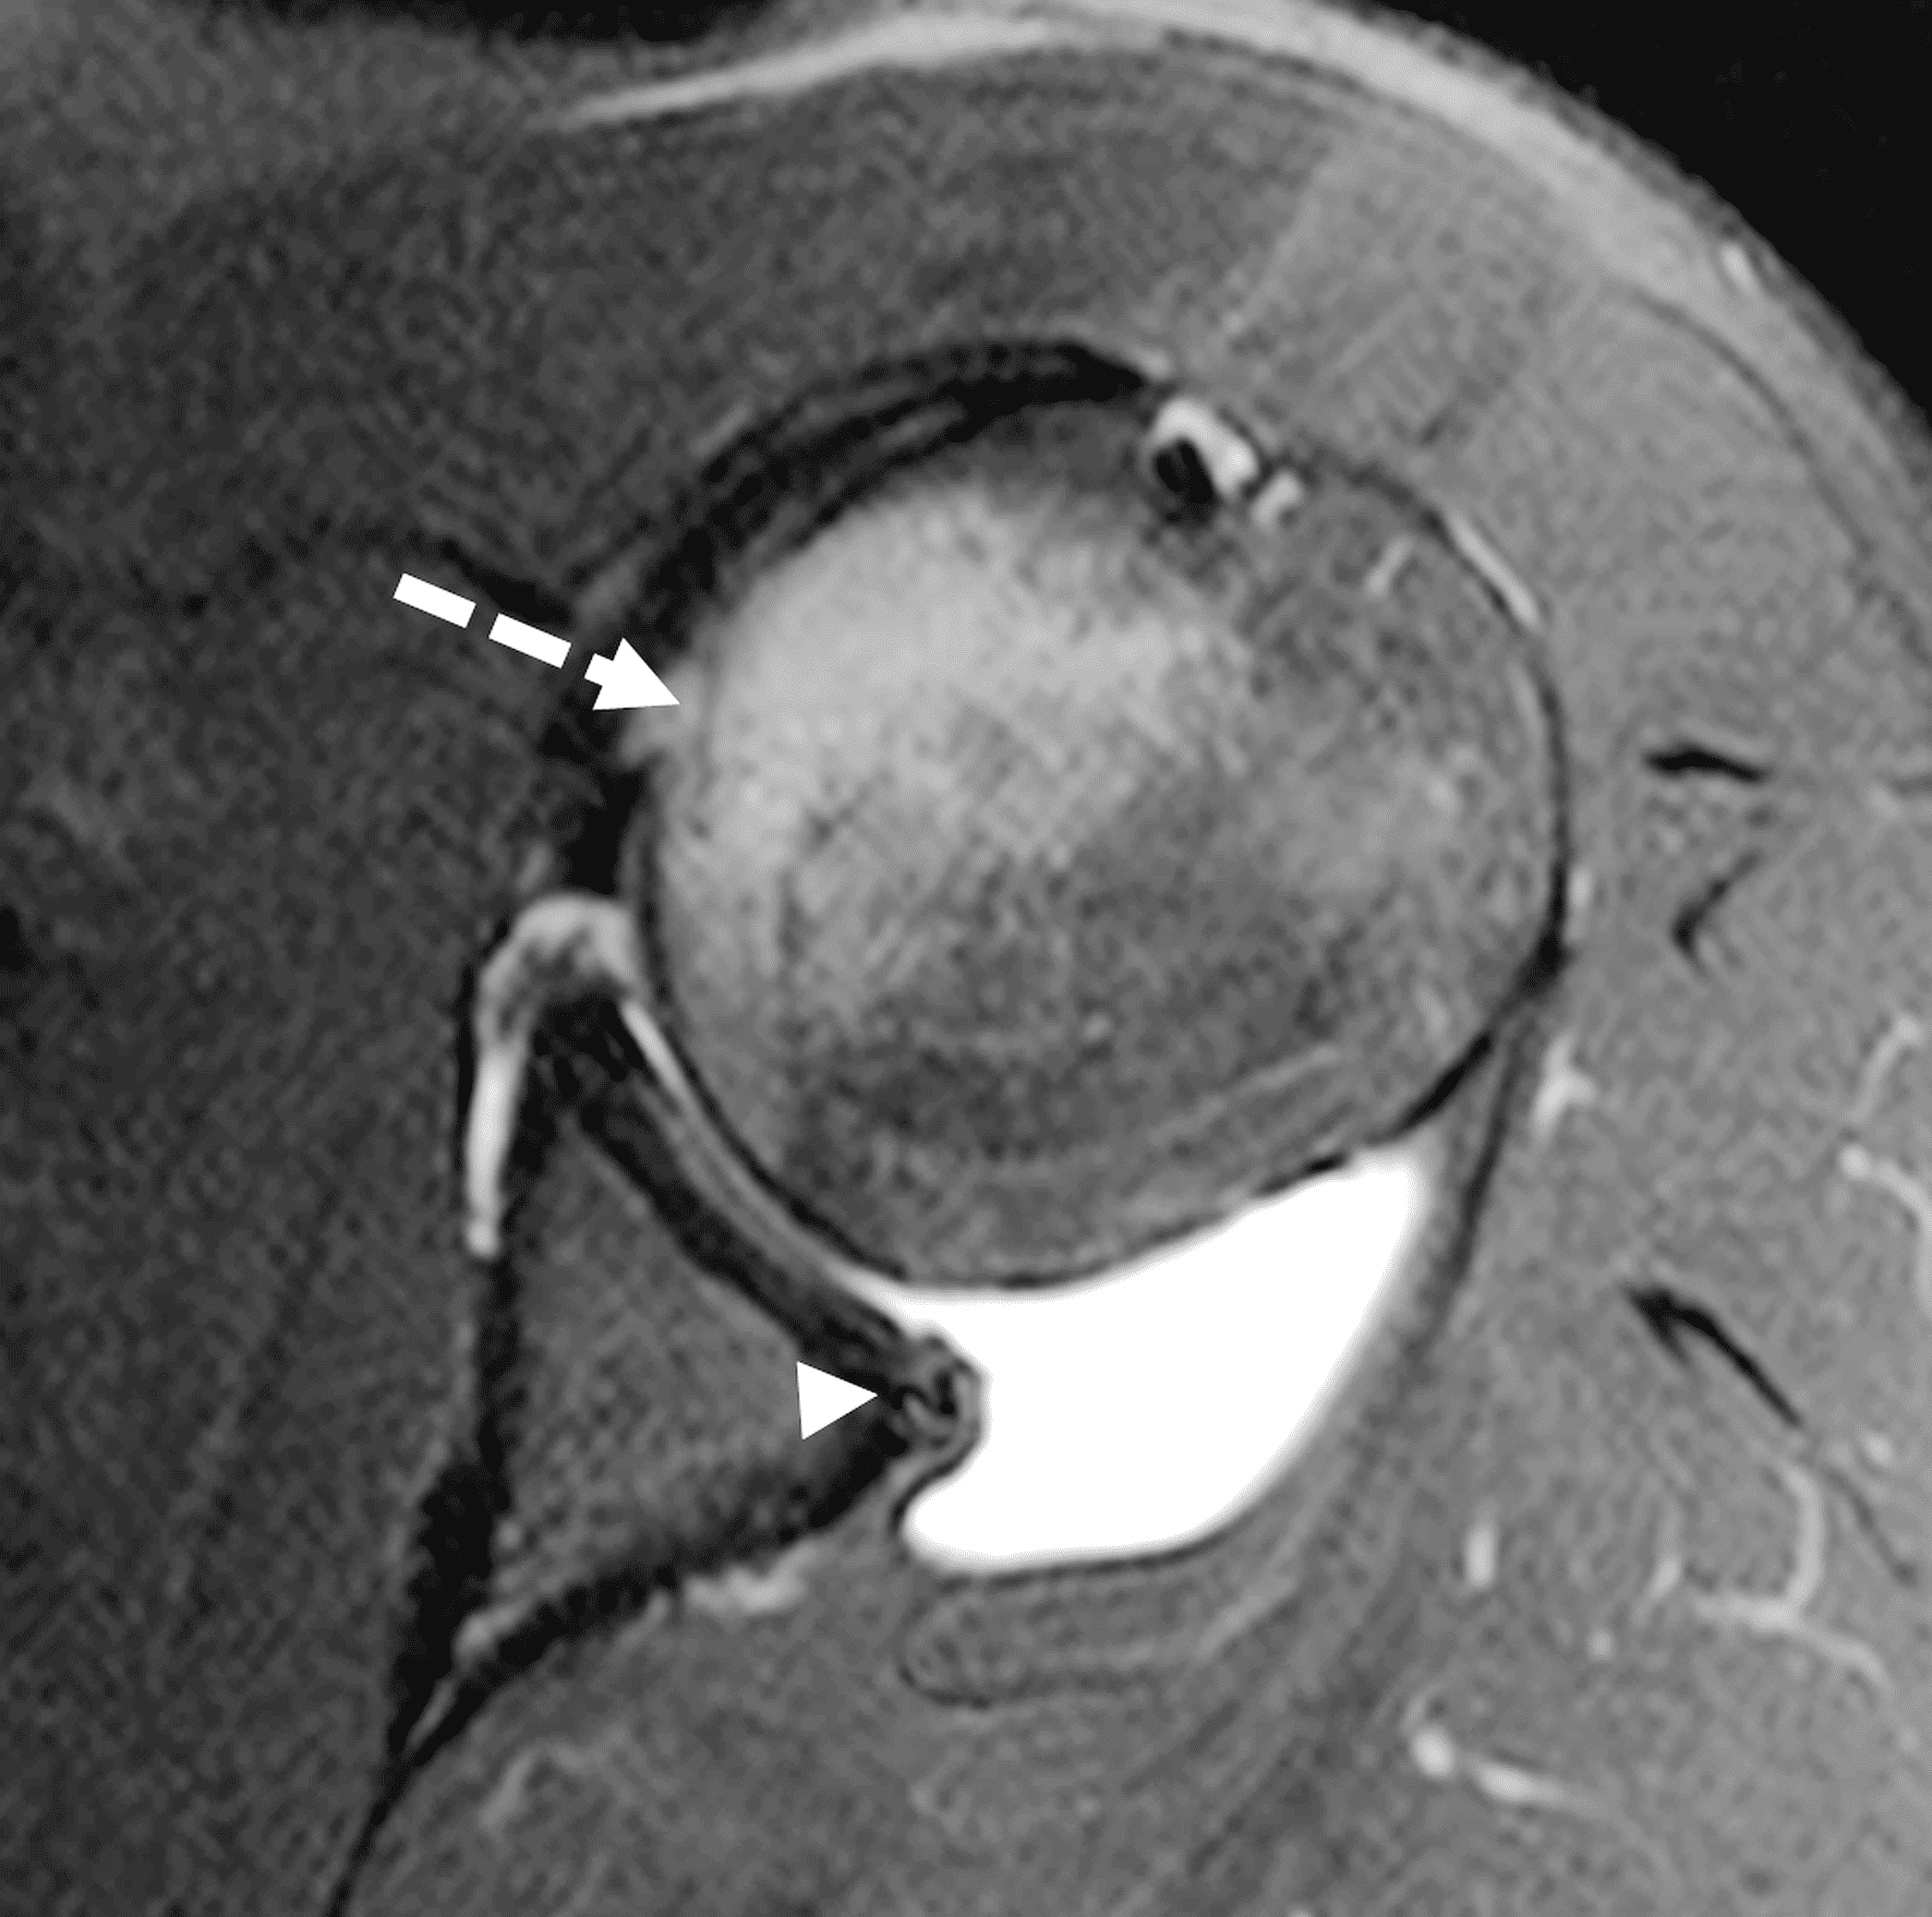

Figure 4: MR arthrogram in a 17-year-old male high school baseball player with acute left shoulder batting injury. (4A) Oblique coronal fat-suppressed T2-weighted image reveals a displaced posteroinferior labral flap (arrow). (4B) Axial fat-suppressed T2-weighted image through the inferior joint confirms the displaced labral flap (solid arrow) and shows a mild anteromedial humeral head impaction injury (dashed arrow). (4C) An axial image more cranially shows ill-defined posteroinferior labral tearing (arrowhead) and marrow edema in the anteromedial humeral head due to the impaction injury (dashed arrow).